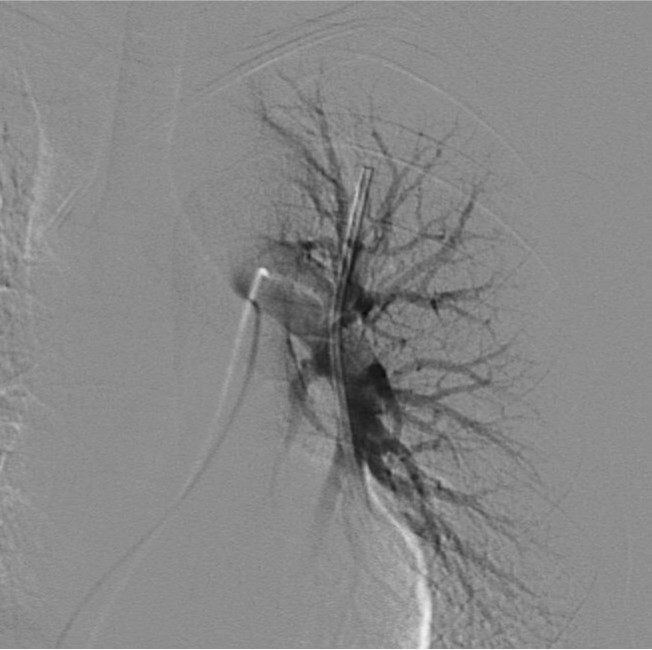

Fig. 3. Pulmonary arteriogram shows the fragmented catheter is positioned in man trunk of the left pulmonary artery

Fig. 4. A

Fig. 4A-E. Retrieval procedure of fragmented chemoport catheter. (A) capture of the fragmented catheter with a 5Fr pigtail catheter.